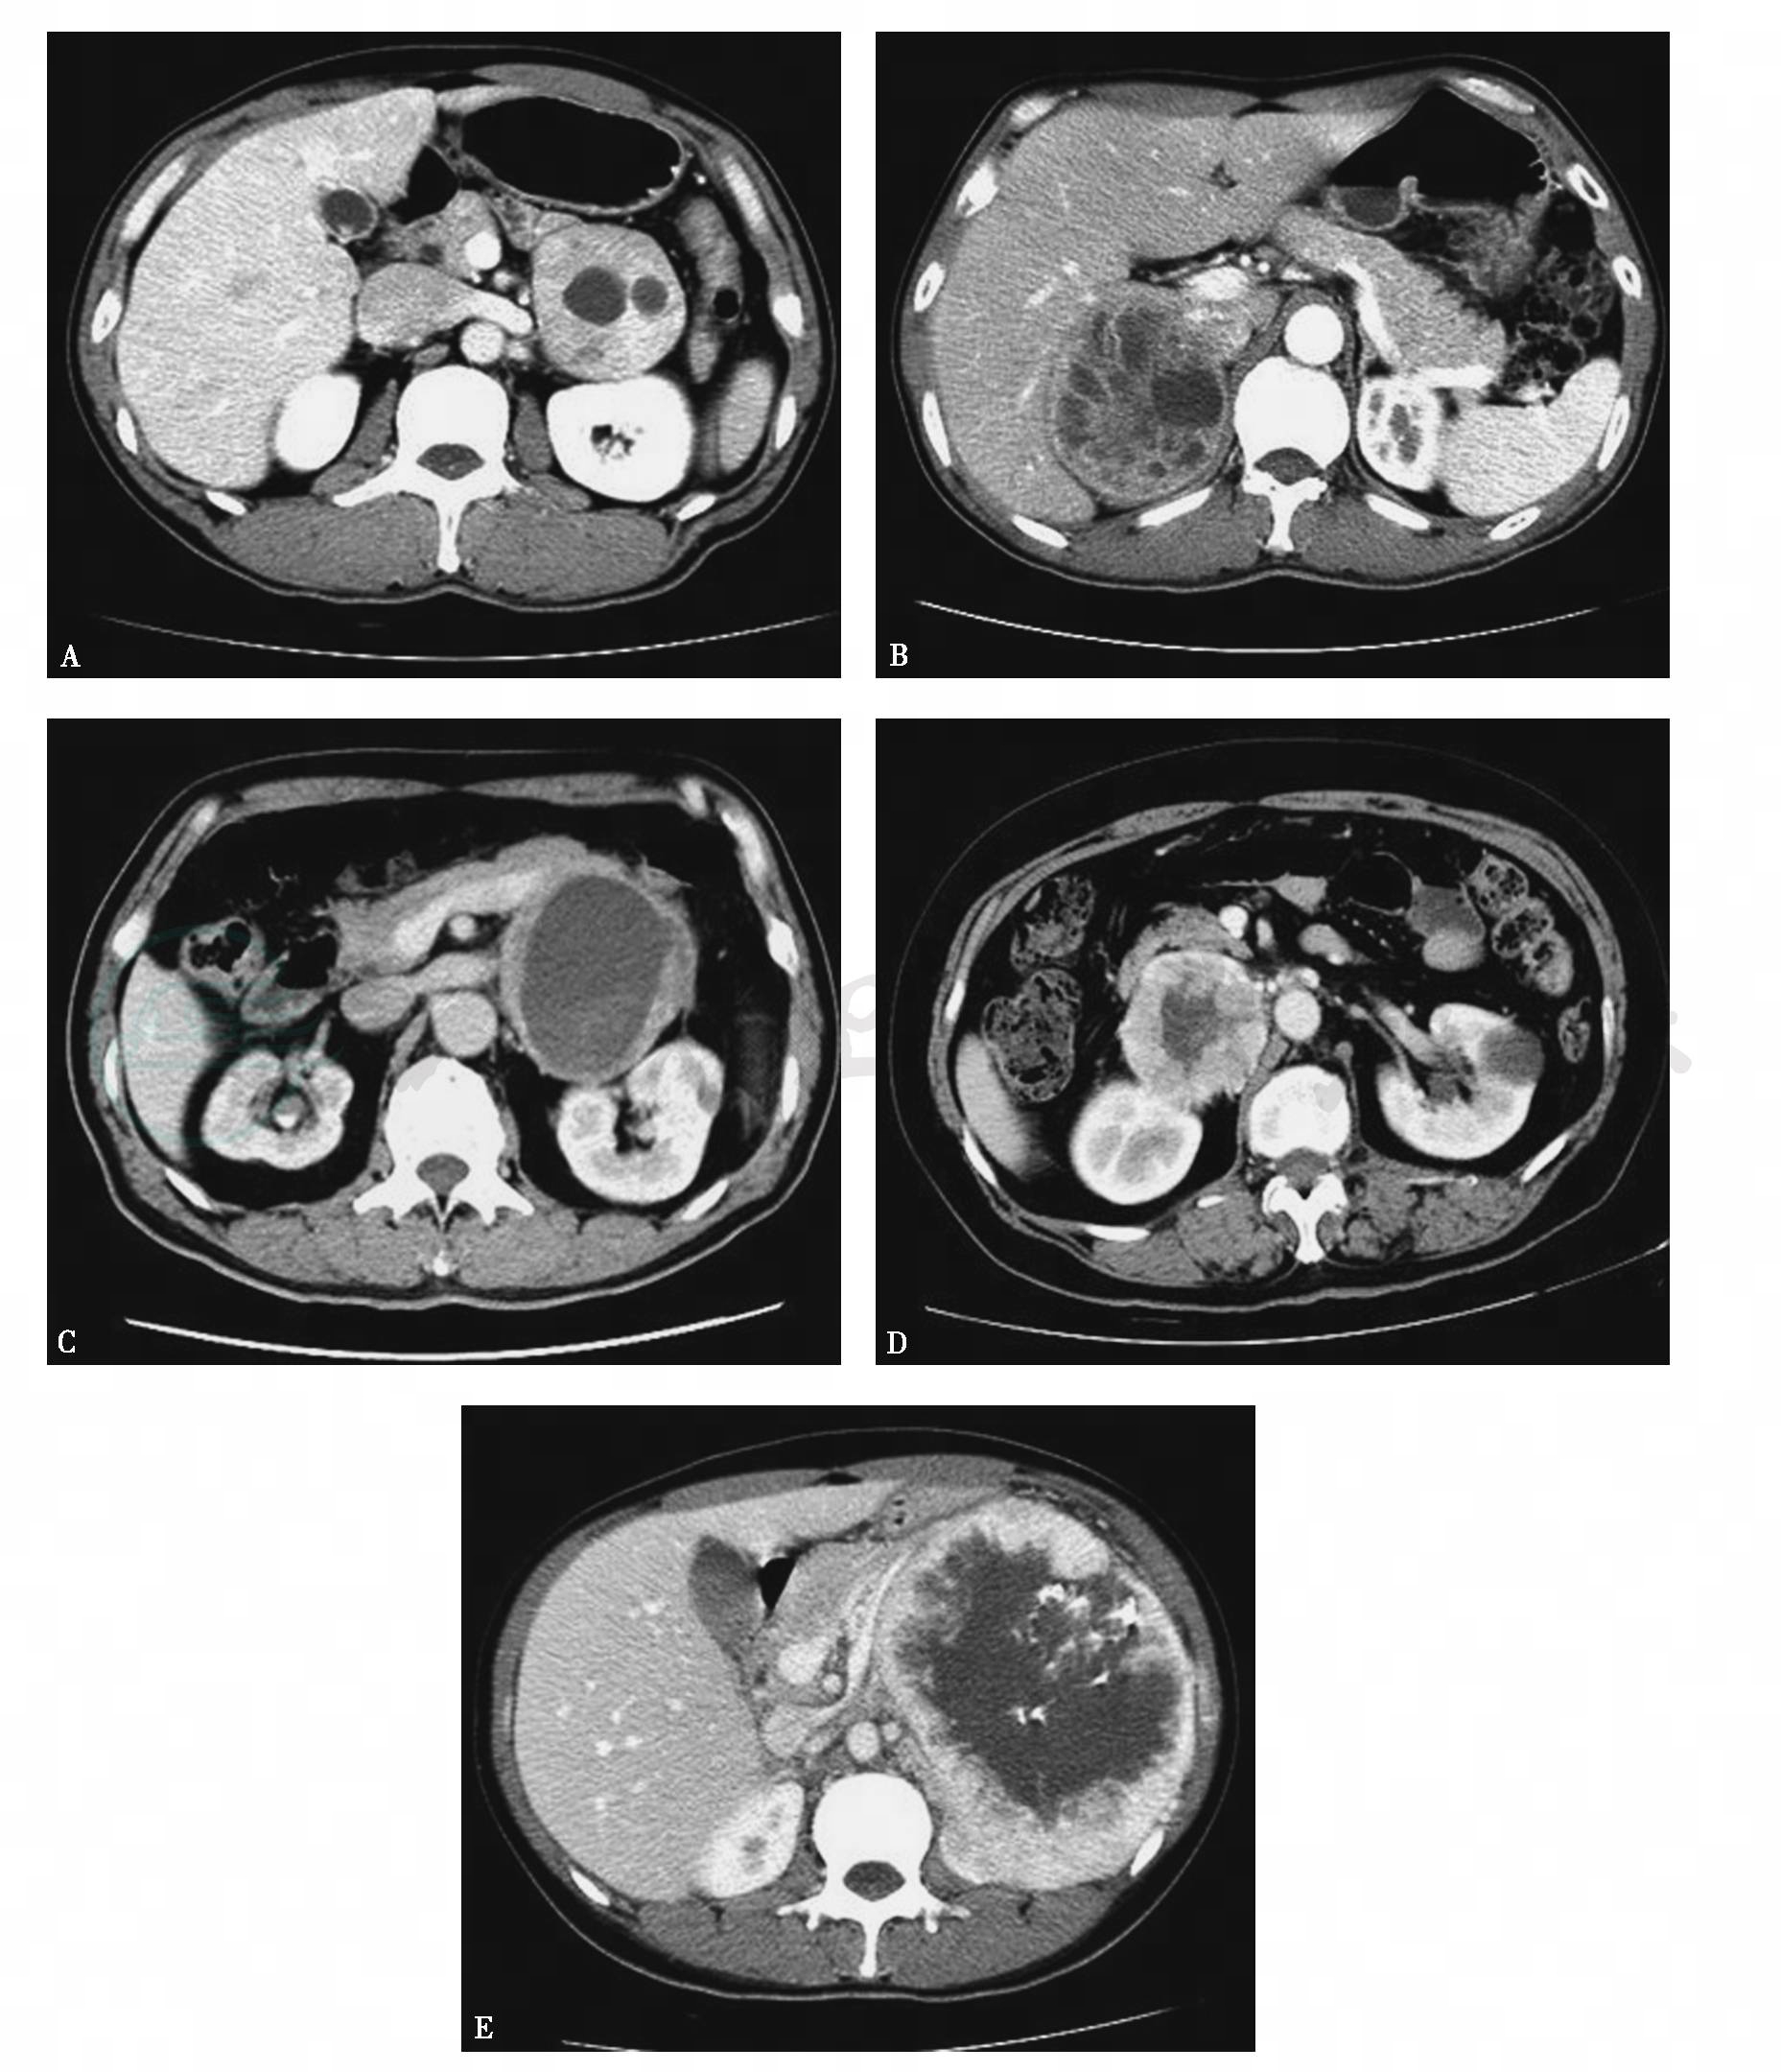

图13中央-边缘坏死

A~D.良性嗜铬细胞瘤不同形态及分布的坏死;E.左侧恶性嗜铬细胞瘤的伴中央-边缘坏死